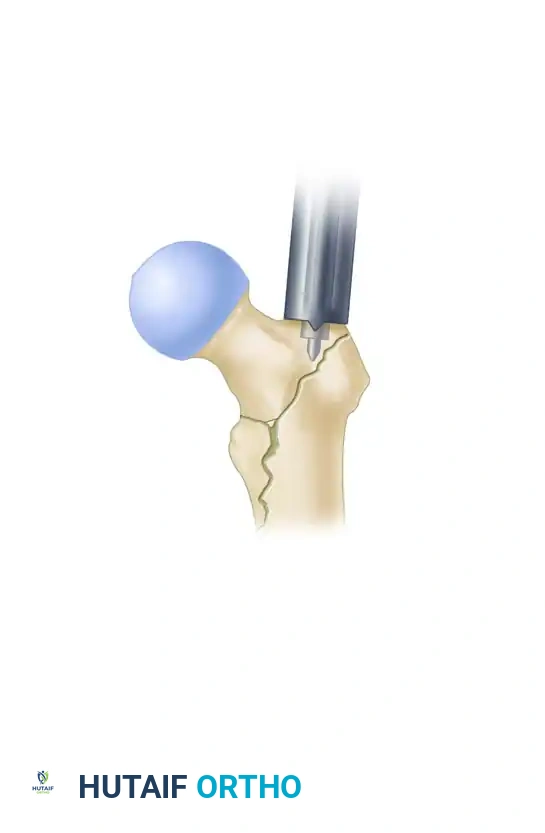

1. The Modified Medial Trochanteric Entry Portal

For the fixation of intertrochanteric femoral fractures, the selection of the entry portal is arguably the most critical step of the operation. We advocate for the modified medial trochanteric portal.

Anatomical Landmarks: The modified medial trochanteric portal is located on the medial aspect of the greater trochanter, directly along the trochanteric ridge on the AP view, and perfectly in line with the central axis of the femoral shaft on the lateral view.

2. Incision and Guide Pin Placement

- Make an approximately 3-cm longitudinal incision, beginning 3 cm proximal to the tip of the greater trochanter and extending proximally. (Note: This incision may need to be extended in morbidly obese patients).

- Sharply incise the fascia lata and the aponeurosis of the gluteus maximus in line with the skin incision. Bluntly split the abductor muscle fibers to palpate the trochanteric tip.

- Localize the entry point with a guide pin on the medial aspect of the greater trochanter.

- Insert the guide pin 2 to 3 cm distally into the proximal fragment.

At this juncture, utilize fluoroscopy to rigorously assess the guide pin placement in both AP and lateral planes.